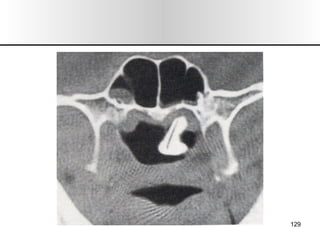

EXPLORACION 1.- Inspección/ Palpación:  Forma, color, alt. Dermicas, movilidad, dolor, inspiración forzada (colapso alar). 2.- Rinoscopia Ant: Desvios, esporones, cornetes, polipos  (solitario),  secreciones, perforaciones, CE, tumores. 3.- Rinoscopia Post: Hipertrofia cornetes, tumores. 4.- Tacto de Cavum: Adenoides. 5.- Rinonanometria: Dif de presión entre vestíbulo y coanas, flujo de vol. 6.- Exp. Radiológica : mentonasoplaca, frontonasoplaca, perfil, axial de Hirtz o submentovertex. TAC, RMN. 7.- Endoscopia Rinusinusal. 8.- Pruebas Alergologicas: pruebas cutaneas, eosinofilia, exudado nasal. SEMIOLOGIA

EXPLORACION 1.- Inspección/Palpación: Forma, color, alt. Dermicas, movilidad, dolor, inspiración forzada (colapso alar). 2.- Rinoscopia Ant: Desvios, esporones, cornetes, polipos (solitario), secreciones, perforaciones, CE, tumores. 3.- Rinoscopia Post: Hipertrofia cornetes, tumores. 4.- Tacto de Cavum: Adenoides. 5.- Rinonanometria: Dif de presión entre vestíbulo y coanas, flujo de vol. 6.- Exp. Radiológica : mentonasoplaca, frontonasoplaca, perfil, axial de Hirtz o submentovertex. TAC, RMN. 7.- Endoscopia Rinusinusal. 8.- Pruebas Alergologicas: pruebas cutaneas, eosinofilia, exudado nasal. SEMIOLOGIA